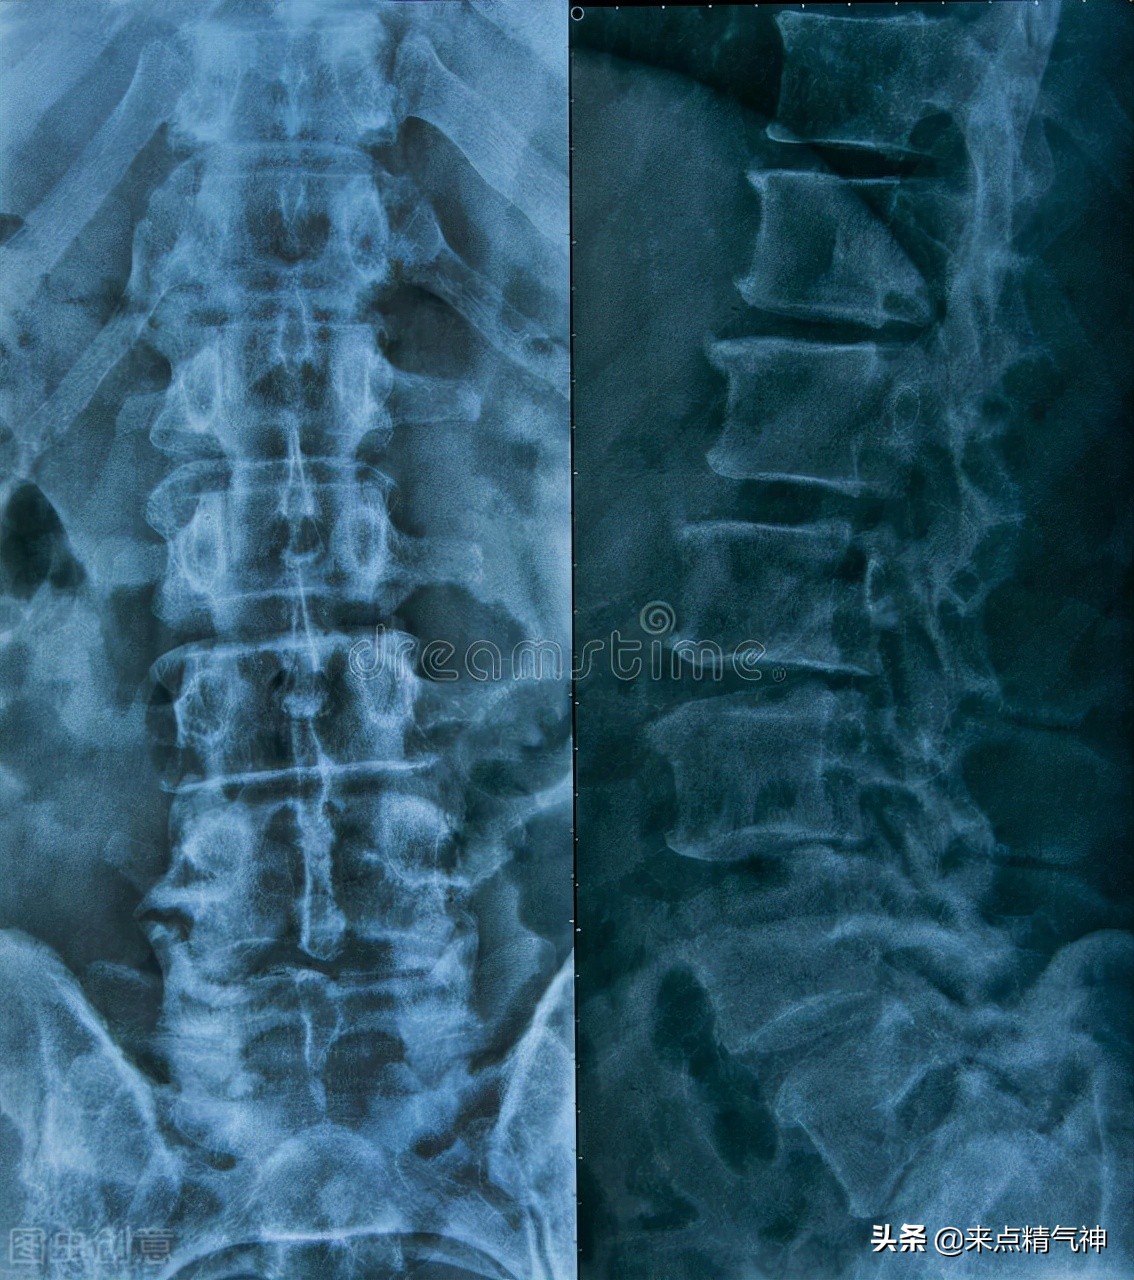

当腰椎结核的病变发展到一定程度后,就会出现腰椎椎体破坏、塌陷并产生变形的情况,由此会造成腰椎后突畸形非常明显。腰椎结核与身体其他部位发生的结核病症一样,也都属于是肺结核细菌引起的疾病。

当发生腰椎结核后,如果没有得到及时治疗,病变的部位会随着椎体蔓延至相邻部位,因此本病最大的特点就是对椎间盘形成破坏性。患病后,患者一般会表现出以下四种明显症状。